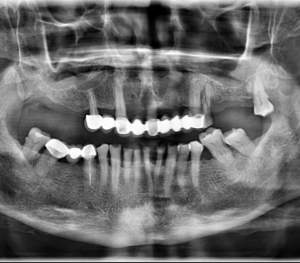

Más de 200 casos clasificados por especialidades y patologías

El alargamiento del proceso estilohioideo está históricamente asociado con dos variantes del síndrome de eagle. En 1937, Eagle propuso dos síndromes asociados con un proceso